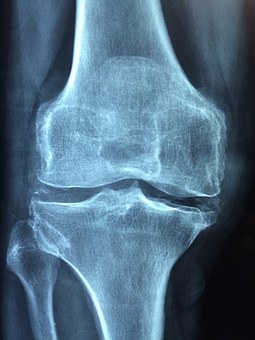

뼈의 강도가 약해져서 쉽게 골절되는 골격계 질환이다. 나이가 들면서 뼈 속의 칼슘이 밖으로 빠져나가게 되면서 노화가 주 원인이다. 여성의 경우 폐경 후 골 소실이 급속히 일어난다. 이는 여성 호르몬의 결핍 때문이다. 손목뼈, 척추, 고관절에서 골절이 자주 발생한다.

골다공증의 원인으로 볼 수 있는 요인은 영양부족, 운동부족, 유전적요인, 만성질환의 유무, 약물복용, 음주와 흡연, 저체중 등 다양하다.

전문의의 진찰과 골밀도 검사, 혈액검사, 소변검사 등이 필요하다.

현재 골다공증을 치료해 완화할 수 있는 치료법은 따로 없다. 따라서, 칼슘섭취와 운동 등 예방활동을 해야 한다. 칼슘과 비타민D는 뼈의 건강에 가장 중요한 영양소이기 때문에 잘 챙겨먹는 것이 좋다. 또, 시력을 교정하고 목욕탕, 계단 등에서 조심하는 등 여러 가지 주의가 필요하다.